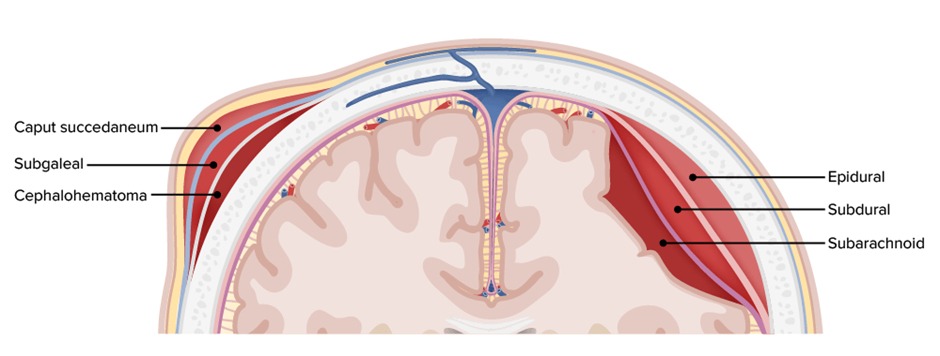

- Subdural hematoma (SDH) is usually secondary to traumatic head injury

- CT shows a crescent shaped collection of blood that DOES cross the suture lines. The midline might shift in some cases